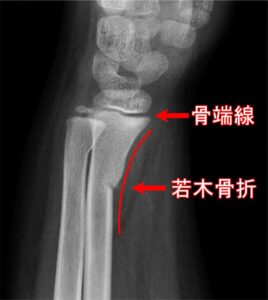

成長期(成長途中)の骨は大人の骨と違い弾力性があり「パキンッ」とはならず、曲がりはすれど折れて分裂することはほどんどありません。

これは、変形中ということで芯はありますが軟らかい状態というのが理由です。

湿気た木の枝や若木の枝を折ろうと曲げた時に「ぐい~ん」と曲がるだけで折れなかったという経験をされたことがあれば想像がしやすいと思います。

このような生理的な特徴もあり、いわゆる“けが(急性外傷)”のように一回で起こることはなく、スポーツの練習などで繰り返し腰椎を反らしたりひねったりすることで起こります。